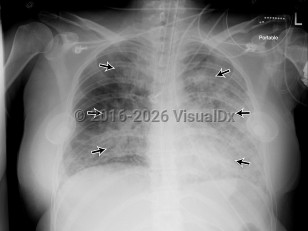

Anasarca, 50-59 year old Female

Congestive heart failureCongestive heart failure

Pericardial effusionPericardial effusion

Acute respiratory distress syndromeAcute respiratory distress syndrome